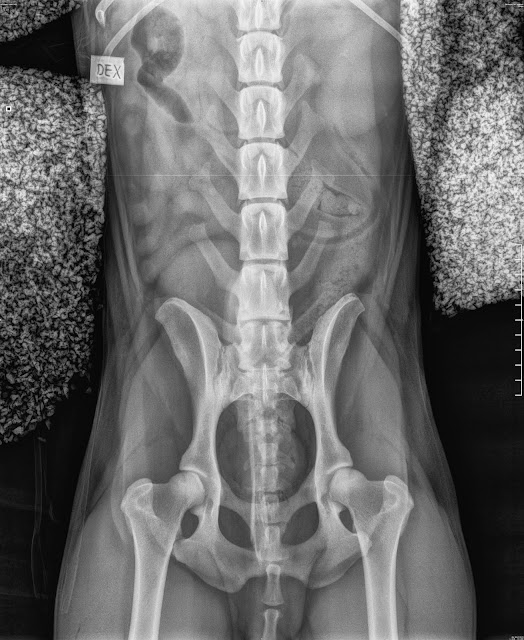

Vaajakosken Univettiin. Saatiin aika samalle päivälle, eläinlääkäri Kalle Varesmaalle, joka hoiti Sakua viime syksynäkin. Sakun koko ruoto kuvattiin. Näin Kalle Varesmaa kirjoittaa Sakusta:

Koko rangan sekä lantioalueen kuvaus: L1-2 välissä mahd. spondyloosimuutos, joka selittäisi sen alueen voimakkaan kipureaktion palpaatiossa. Reaktio kaularangan taivutuksessa voi johtua samaisesta muutoksesta lannerangan alueella.

Sitten VD kuvat:

|

| Lantio |